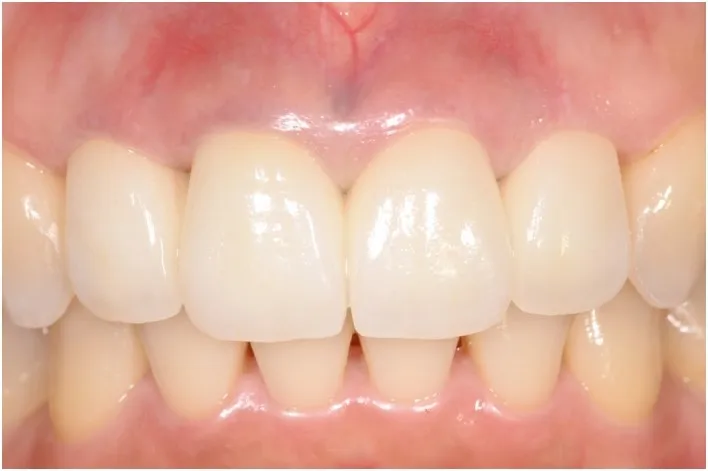

【治療後】